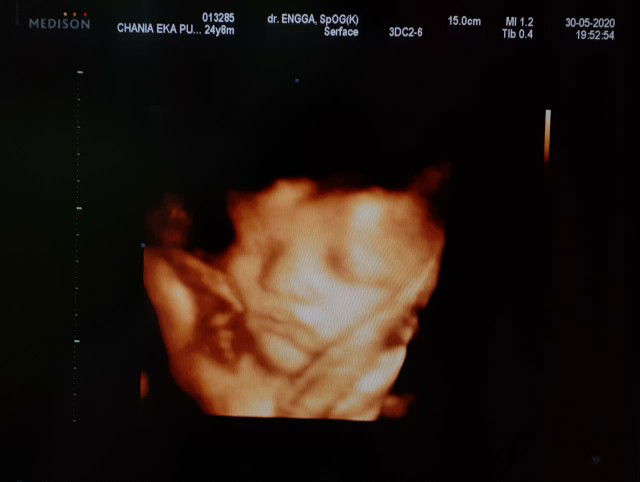

boleh, pak. Yg penting ga di salah gunakan aja aplikasinya, kalo hanya sekedar bertanya seputar rumah tangga, memantau kehamilan istri, memantau perkembangan janin dan anak boleh banget kok, kan nama aplikasinya the asian parents, brrt semua org tua baik ayah atau ibu bisa pake aplikasi ini , semoga membantu